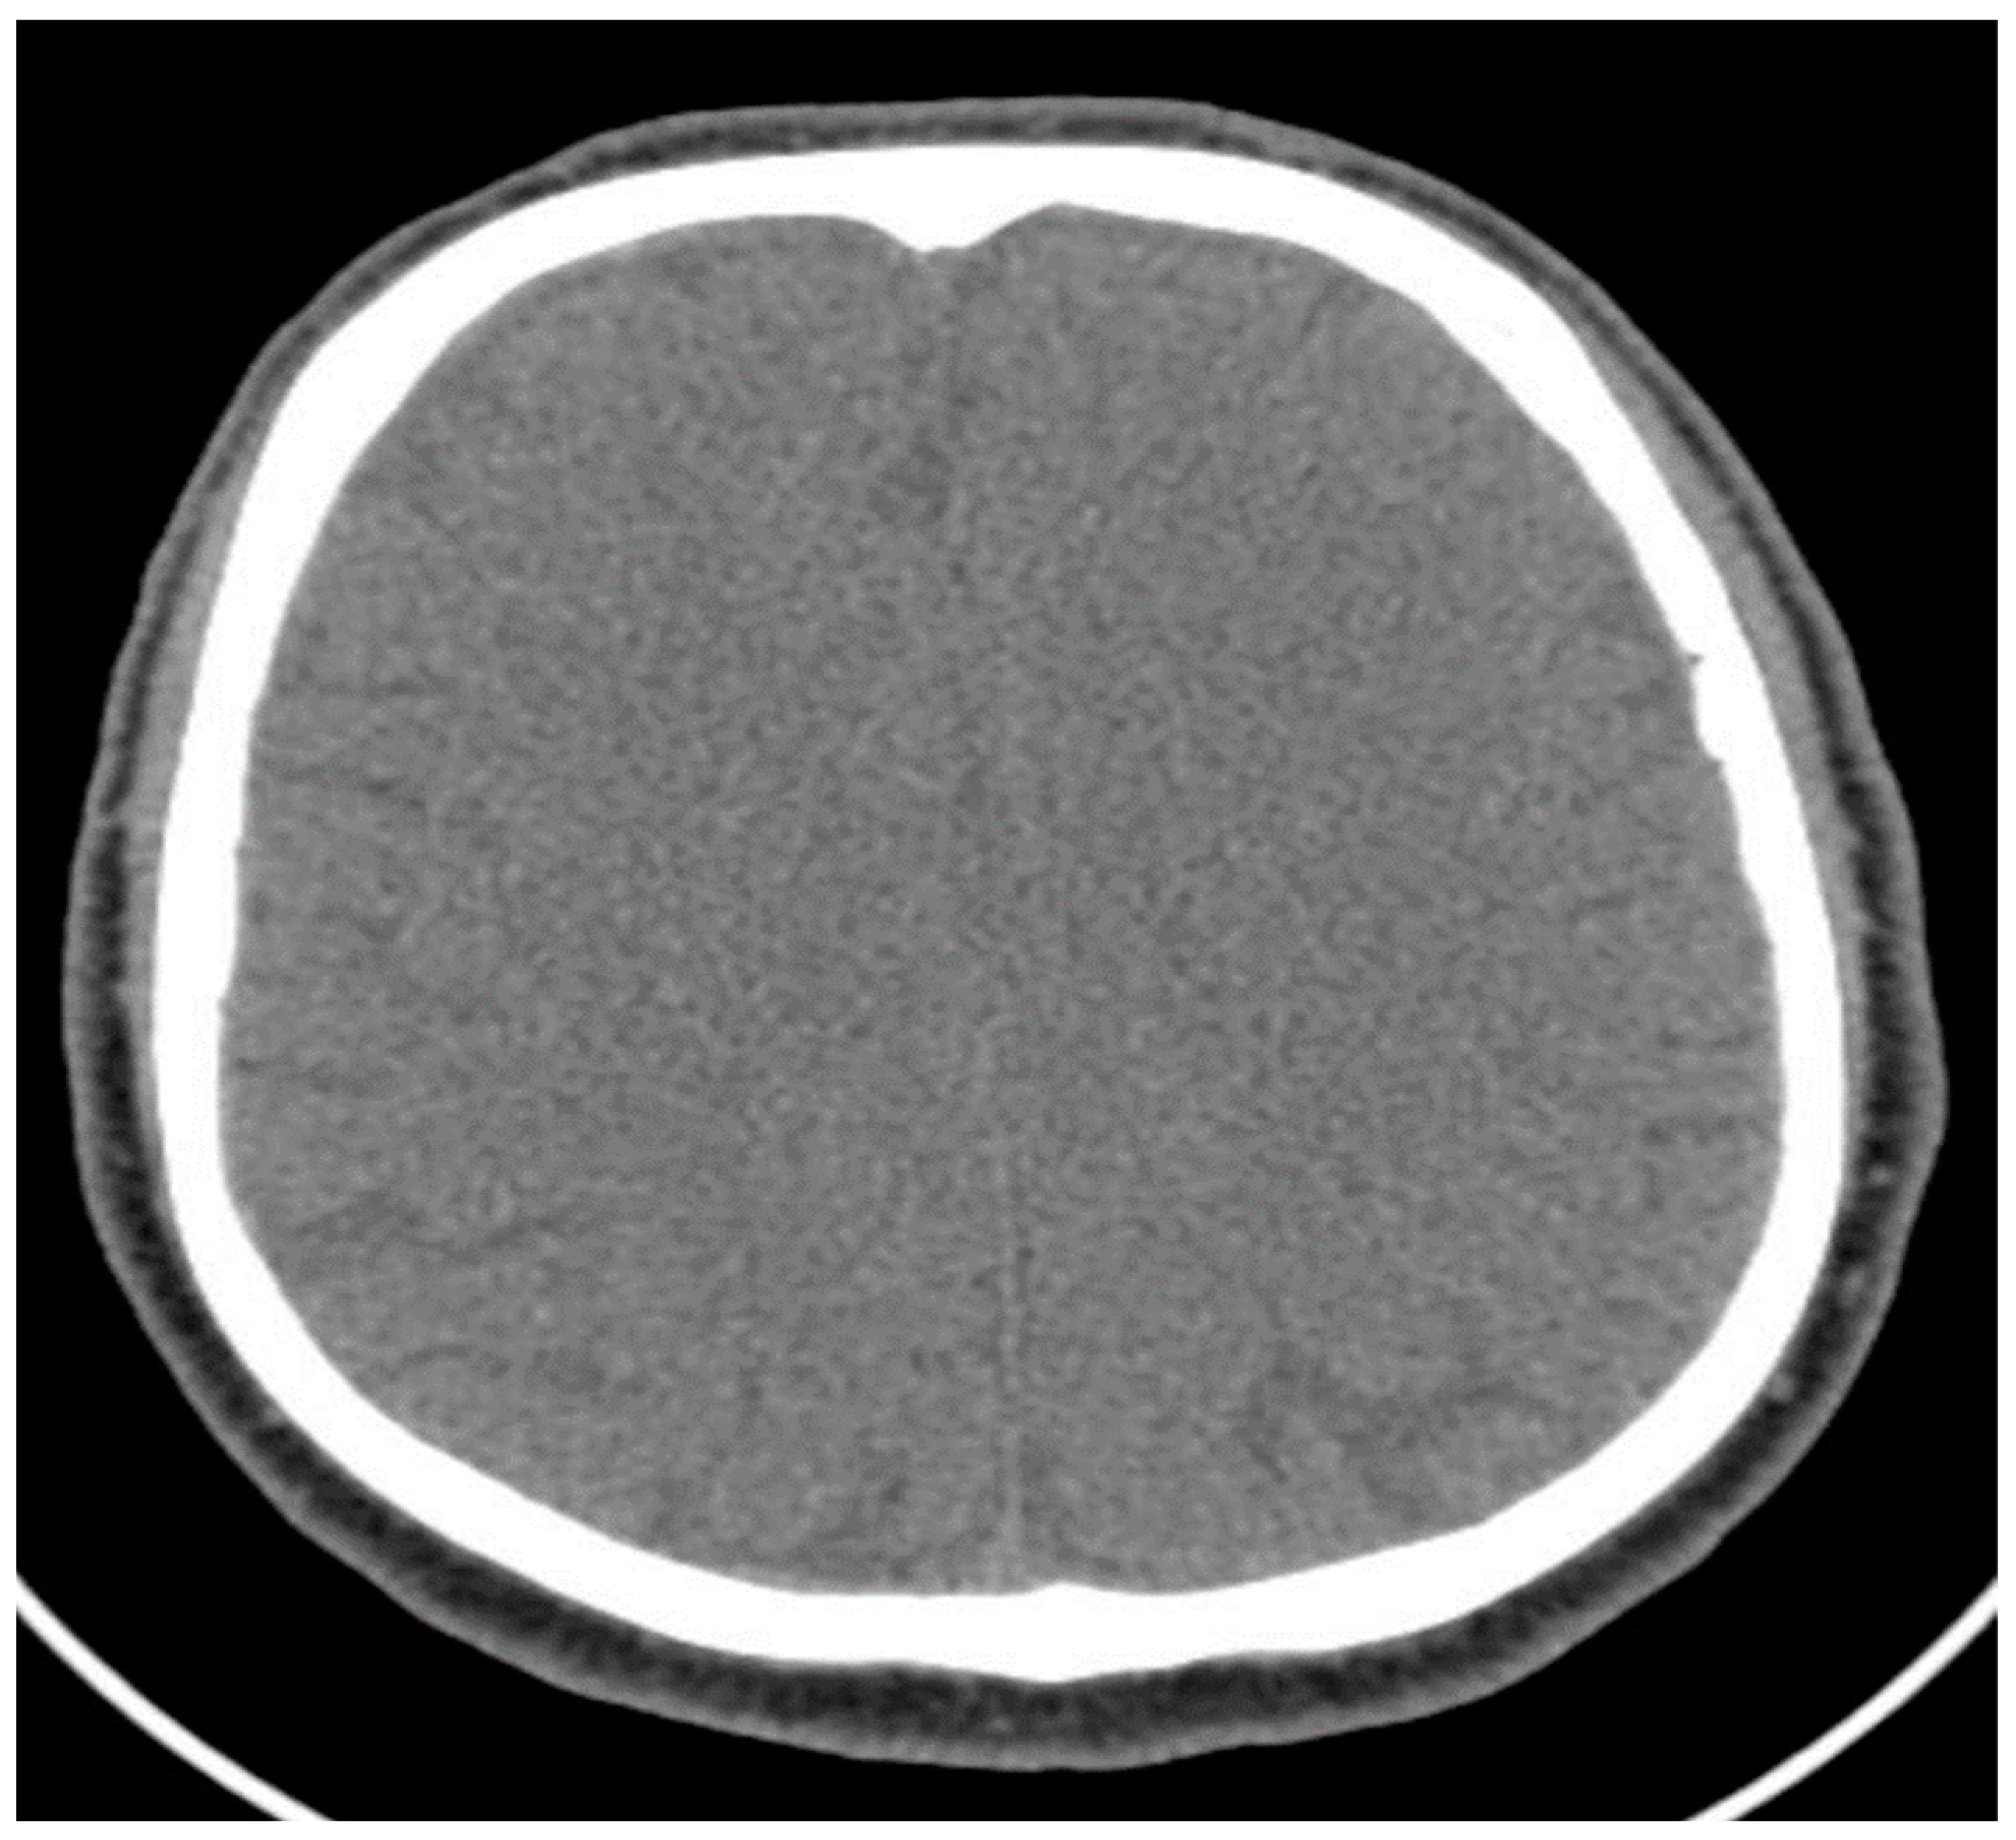

- Psycho-organic syndrome: This was ruled out by the absence of changes on the computerized tomography scan; memory and attention disorders were secondary to the depression.